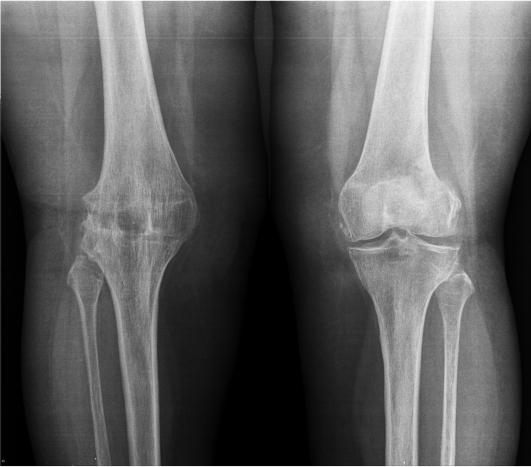

Рентгеновские снимки анкилоза суставов: Как это выглядит